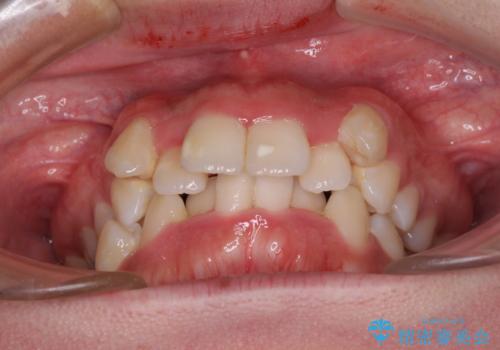

- 上下の八重歯やデコボコを気にして来院された患者様です。

上下ともに八重歯が顕著であったので、上下左右第一小臼歯4本を抜歯し、補助装置を使用して速やかに改善しながら、ワイヤー装置にて矯正治療を行うこととしました。